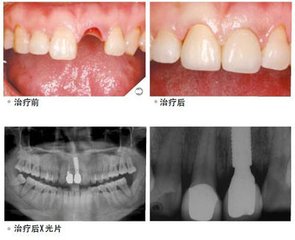

我的牙齿真的“重生”了

综合分析了她的失牙后牙槽骨及牙床的变化情况后,为她设计了一套个性化的种植方案。首先在她原来牙槽窝内钻个小孔,然后将人工牙根植入其中,并测量植入的人工牙根有足够稳固性,整个手术过程小艺没有感觉到任何痛苦。如今,她新“长”的牙齿和其他的自然牙一样和谐统一。她高兴的说:“人工种植牙真好,跟真牙完全一样,不怕酸不畏冷,既舒适美观又避免了假牙的清洁麻烦和影响发音的缺陷。现在我的牙齿真的‘重生’了”。